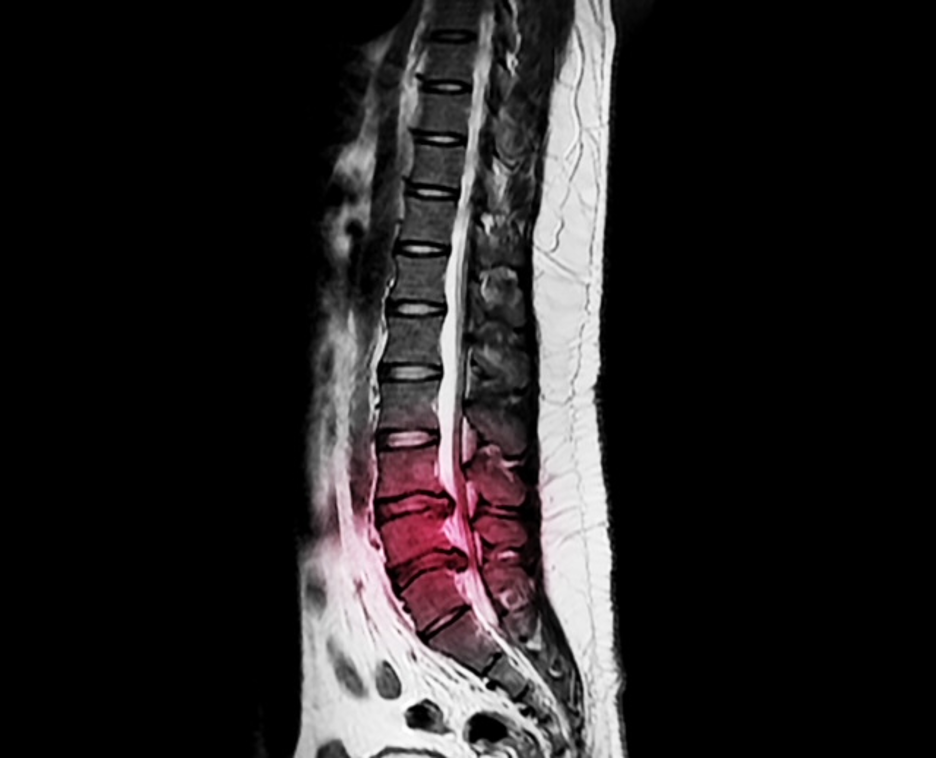

To diagnose a lumbar herniated disc, your neurosurgeon usually performs a history and physical examination. If necessary, your neurosurgeon might order a diagnostic test such as a lumbar MRI, Lumbar CT scan or lumbar CT/Myelogram.